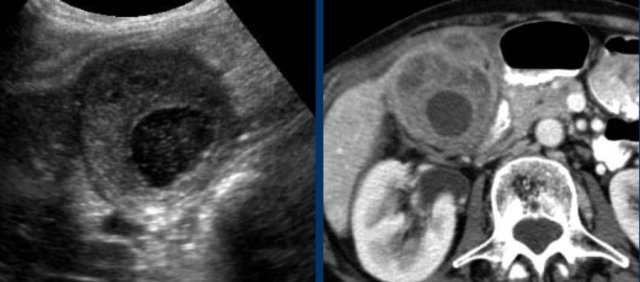

Here images of a patient with clinically suspected stomach perforation.

CT shows some stones in a rounded gallbladder.

Complementary US unequivocally demonstrates hydrops (arrowheads).